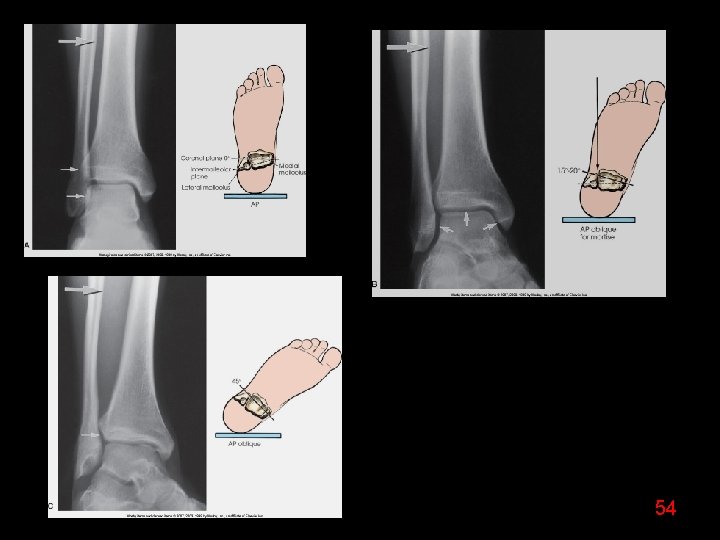

54

WHICH OBLIQUE ? 55